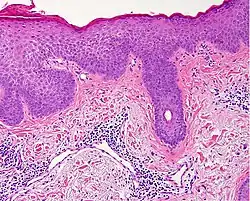

Interface dermatitis with lichenoid inflammation

| Main conditions[2] | Characteristics | Micrograph | Photograph |

|---|---|---|---|

| Generally/Not otherwise specified | Typical findings:[2]

|

||

| Lichen planus | Irregular epidermal hyperplasia with a jagged "sawtooth" appearance, compact hyperkeratosis or orthokeratosis, foci of wedge-shaped hypergranulosis, basilar vacuolar degeneration, slight spongiosis in the spinous layer, and squamatization. The dermal papillae between the elongated rete ridges are frequently dome shaped. Necrotic keratinocytes can be observed in the basal layer of the epidermis and at the dermal-epidermal junction. Eosinophilic remnants of anucleate apoptotic basal cells may also be found in the dermis and are referred to as "colloid or civatte bodies". Whickham striae are usually seen in the areas of hypergranulosis. Vacuolar degeneration at the basal layer may be noted leading to focal subepidermal clefts (Max Joseph spaces). Squamatization occurs as a result of maturation and flattening of cells in the basal layer. It happens in areas of marked hypergranulosis with prominence of the sawtooth pattern of rete ridges. Wedge-shaped hypergranulosis can occur in the eccrine ducts (acrosyringia) or hair follicles (acrotrichia). In the hypertrophic subtype, the associated hyperkeratosis, parakeratosis, hypergranulosis, papillomatosis, acanthosis, and hyperplasia markedly increased with thicker collagen bundles forming in the dermis. Moreover, the rete ridges are more elongated and rounded as opposed to the typical sawtooth pattern. In atrophic LP, loss of the rete ridges and dermal fibrosis is prominent. In vesiculobullous LP, the disease progression is quicker. Hence, some of the distinctive features such as hyperkeratosis, hypergranulosis, or dense lymphocytic dermal-epidermal infiltrate may not be present. LP lesion may resolve with residual hyperpigmentation caused by a persistent increase in the number of melanophages in the papillary dermis.[9] | ![]() | ![]() |